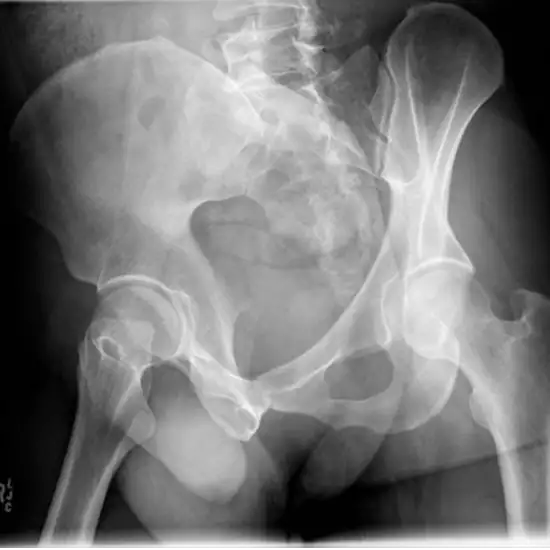

X-Ray Hip Oblique

Imaging the pelvic and hip joints using an X-ray helps identify any abnormalities in the soft tissues (skin and muscles) around the joint.